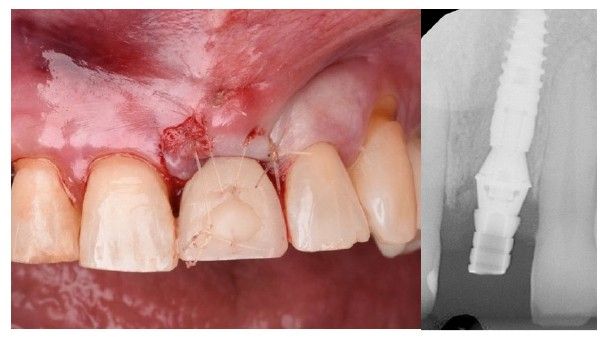

El implante se posicionó aproximadamente 4 mm subgingival en sentido vertical y manteniendo un gap vestibular superior a 2 mm en sentido horizontal (Figura 5). Dicho espacio fue rellenado con un xenoinjerto óseo de origen bovino (Bio-Oss®, Geistlich). A continuación, se realizó un injerto de tejido conectivo, obtenido de la tuberosidad maxilar, mediante una técnica de túnel en la zona vestibular, fijándolo con sutura reabsorbible incolora 5/0 (Monocryl Plus, Ethicon®) (Figura 6).

Tras la colocación del implante, se instaló un pilar transepitelial Klockner® tipo Permanent, recto unitario NV de 2 mm de altura, atornillado con un torque de 30 N/cm. Posteriormente, mediante un casquillo provisional de titanio atornillado, se llevó a cabo la recaptura de la corona provisional tipo “cáscara de huevo” previamente confeccionada por el laboratorio (Figura 7). Para ello, se empleó acrílico autopolimerizable (TAB 2000, Kerr®), seguido de la aplicación de composite fluido (Tetric EvoFlow® A2, Ivoclar Vivadent®) para la conformación progresiva del perfil de emergencia, garantizando un adecuado ajuste, acabado y pulido de la restauración provisional (Figura 8 y 9). Dado que las cargas oclusales resultan desfavorables en este tipo de casos, se redujeron los contactos en máxima intercuspidación y durante los movimientos excursivos en el provisional de carga inmediata, con el objetivo de minimizar los micromovimientos y preservar el éxito del tratamiento. La paciente acudió a revisión a los 15 días para retirada de sutura, sin registrar complicaciones en este periodo de tiempo (Figura 10).

El implante se mantuvo en fase provisional durante un periodo aproximado de cuatro meses desde su colocación. Tras esta fase de provisionalización, se realizó la toma de impresión analógica mediante un coping de impresión personalizado, diseñado para reproducir de forma precisa el perfil de emergencia previamente modelado con la restauración provisional (Figuras 11 y 12). A partir de estos registros, se confeccionó e instaló la corona definitiva atornillada, con una oclusión suavizada para evitar sobrecargas del implante (2.1i). La imagen clínica (Figuras 13 y 14) y el CBCT postoperatorio (Figura 15) evidencian una situación clínica y radiológica favorable, con estabilidad de los tejidos periimplantarios a los cuatro años de seguimiento.